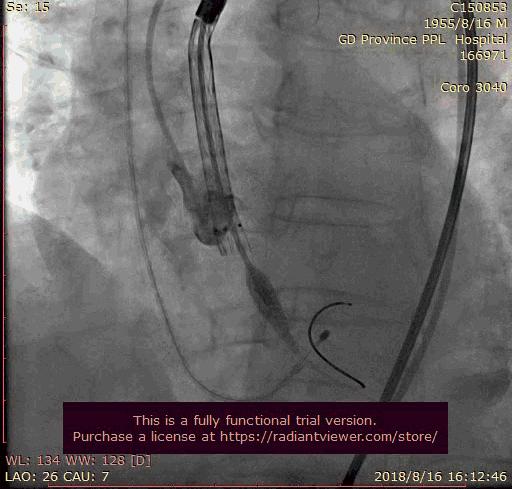

瓣膜释放

最后一枪造影

术后:

瓣膜功能良好,患者主窄解除,主动脉瓣未见明显反流及瓣周漏。术后给予波立维联合达比加群酯抗栓,复查粪、尿常规,未见明显出血,血红蛋白稳定。